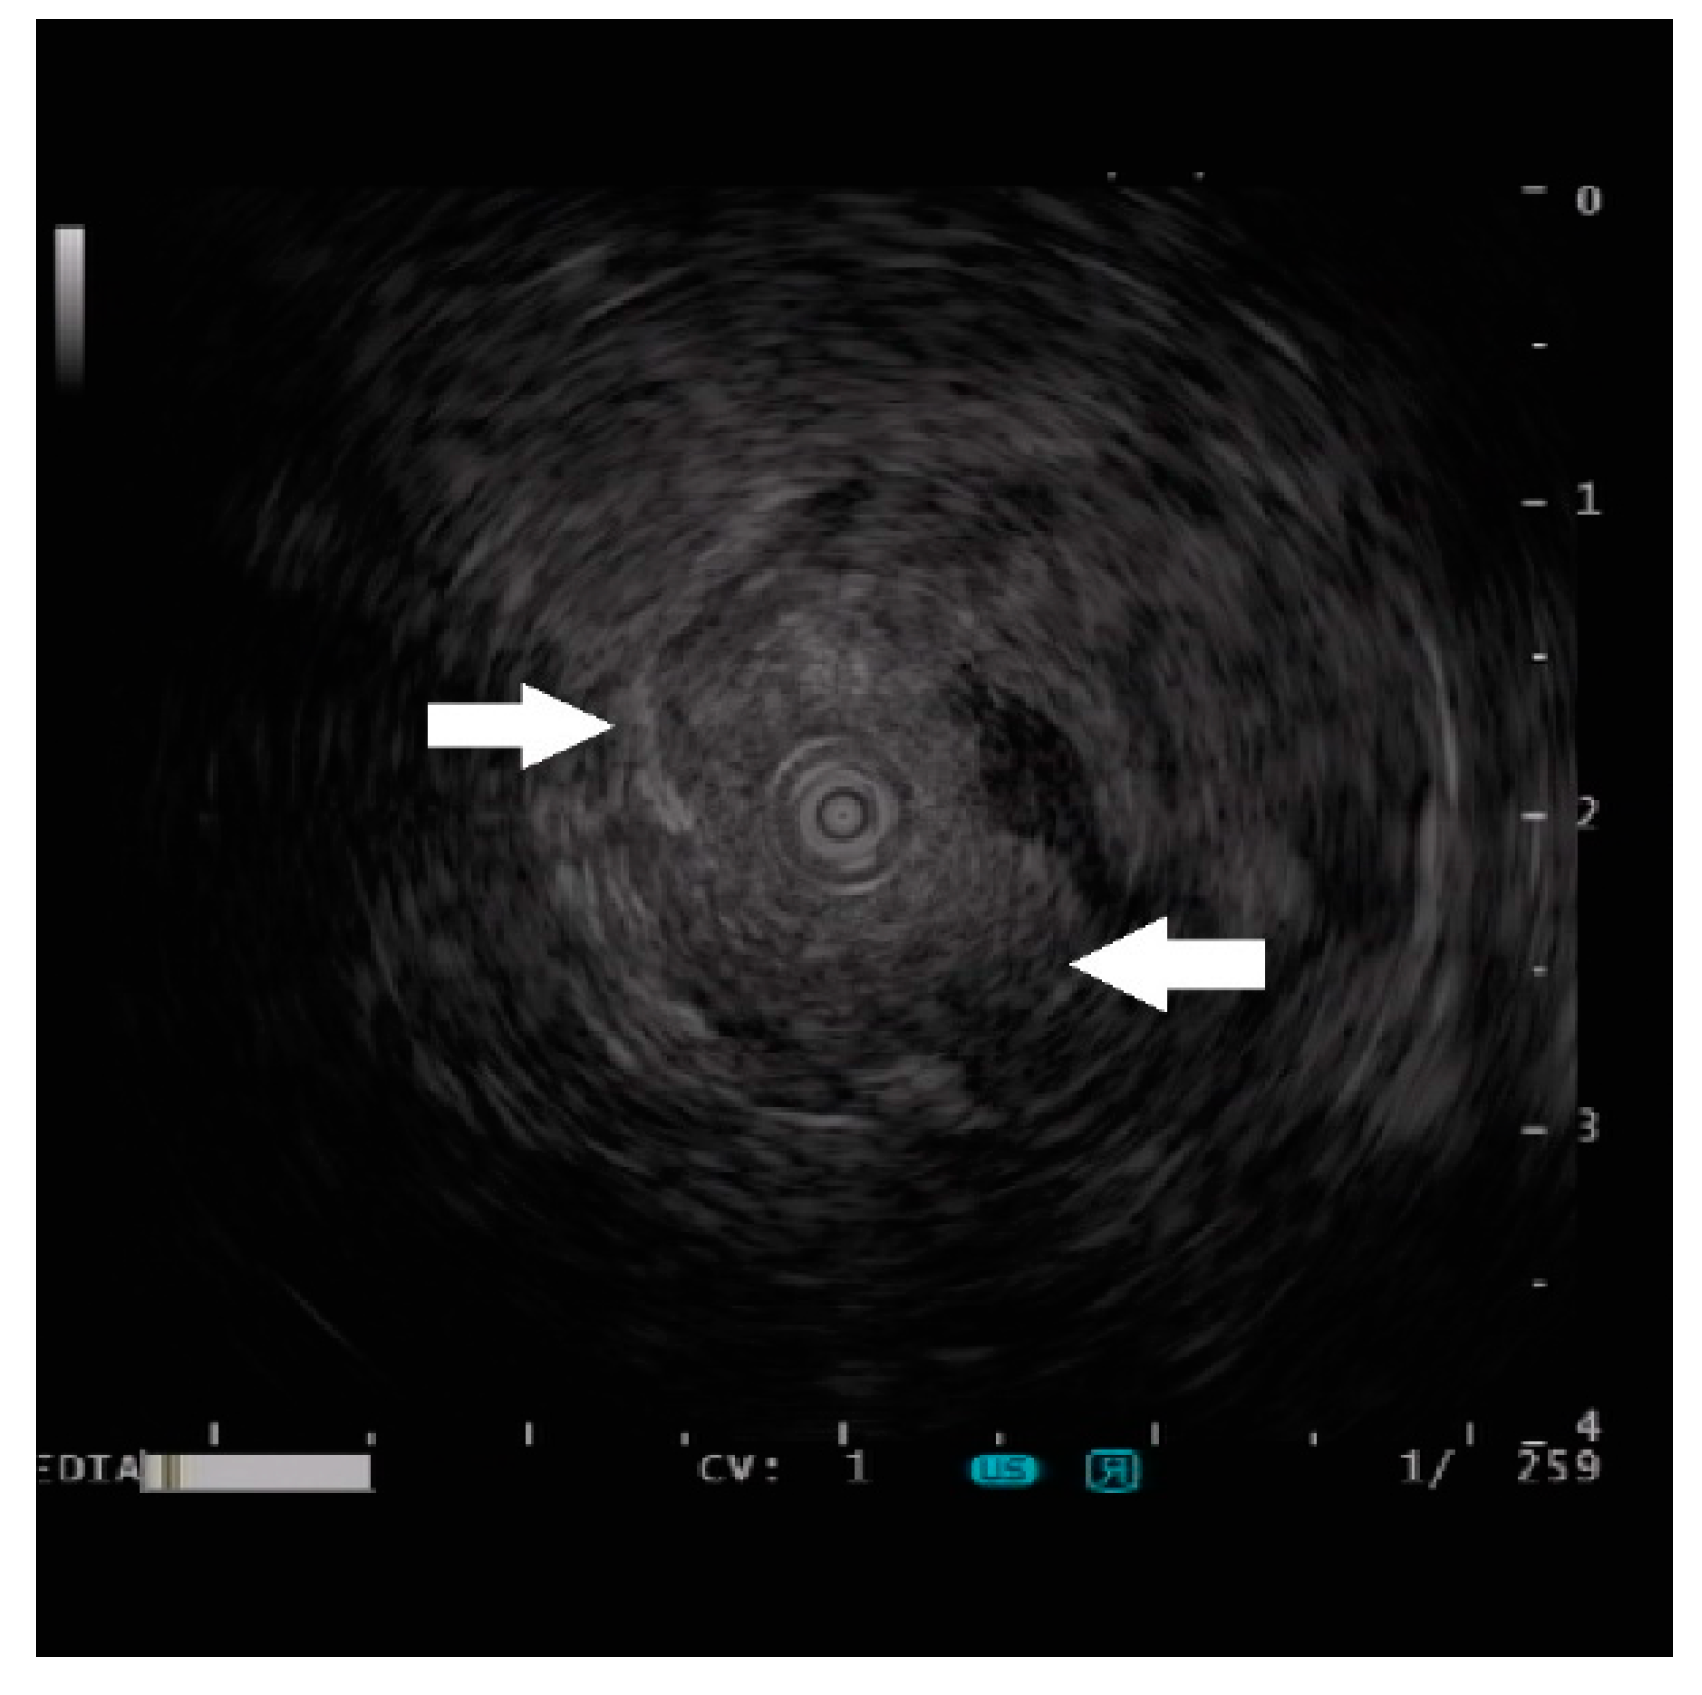

Endoscopic Ultrasound Appearance of Jejunal Ectopic Pancreas Mimicking Metastatic Nodule in a Cancer Patient